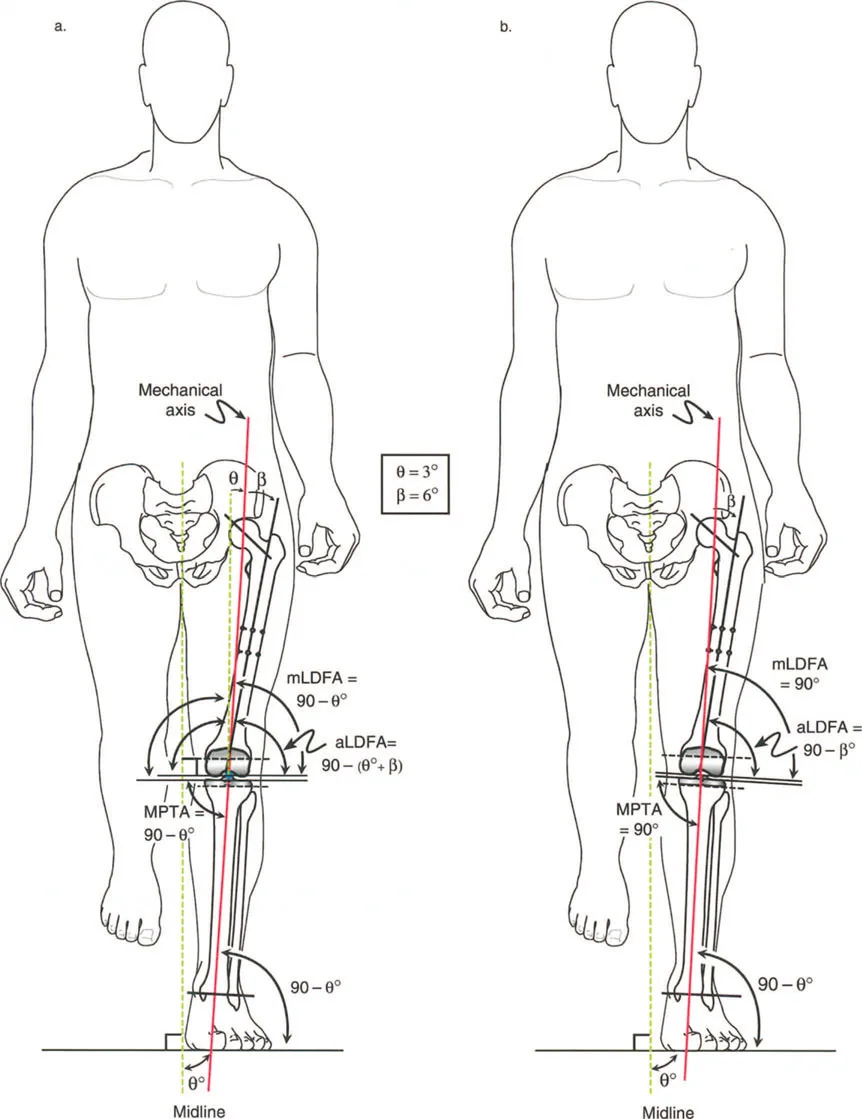

لطالما كان التركيز الأساسي في جراحة العظام، خاصة لطلبة الجراحة، ينصب على التشوهات الثابتة للأطراف السفلية. هذه التشوهات تشمل انحرافات العظام الثابتة، والتئام العظام بشكل خاطئ، وعدم التئامها، وتيبس المفاصل، وهي حالات يسهل قياسها وتحديدها عبر الأشعة السينية الثابتة. ولكن، لكي يتقن الجراح حقًا إعادة بناء الأطراف السفلية، وتخطيط عمليات قطع العظم (Osteotomy)، وجراحات استبدال المفاصل المعقدة، يجب عليه أن يتجاوز هذا الفهم التقليدي ويتعمق في العالم الحركي والسائل للتشوهات الديناميكية.

التشوهات الديناميكية هي اختلالات وظيفية تتأثر بموقع المفصل في الفراغ، ووظيفة العضلات، والأهم من ذلك، الطول الفعلي والتوجيه المكاني لأذرع الرافعة الهيكلية أثناء الحركة. على عكس التشوهات الثابتة التي تكون موجودة بغض النظر عن الحركة، فإن التشوهات الديناميكية تظهر بوضوح أو تتفاقم عندما يحاول المريض أداء حركة معينة، مثل المشي أو الوقوف.

في حين أن التشوهات الديناميكية تُناقش غالبًا في سياق أمراض الأعصاب والعضلات لدى الأطفال، فإن المبادئ البيوميكانيكية التي تحكمها تنطبق عالميًا على إعادة بناء العظام لدى البالغين. يشمل ذلك سيناريوهات إعادة البناء المعقدة للغاية، مثل استبدال مفصل الركبة الكلي (TKR) واستبدال مفصل الورك الكلي (THR) المرتبطة بالانحرافات الشديدة خارج المفصل. إن فهم الأذرع الرافعة هو المتطلب الأساسي لإتقان هذه التقنيات المتقدمة في جراحة المفاصل وقطع العظم، وهو ما يتقنه الأستاذ الدكتور محمد هطيف في ممارسته اليومية.

- الأشعة مع تحمل الوزن (Weight-bearing X-rays): تُظهر كيف تتصرف المفاصل والعظام تحت الضغط الطبيعي للجسم، وهو أمر حيوي لتقييم التشوهات الديناميكية.

- أشعة الأطراف الطويلة (Long Leg Films): تُؤخذ هذه الأشعة من الورك إلى الكاحل في صورة واحدة لتقييم المحور الميكانيكي الكامل للطرف السفلي وتحديد أي انحرافات.